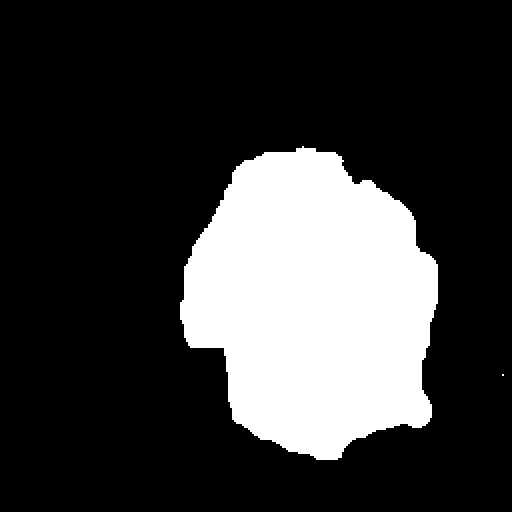

A few sample images and the corresponding masks of the polyp dataset in HyperKvasir are shown in Fig 2. The polyp images are RGB images. The masks of the polyp images are single-channel images with white () for true pixels, which represent polyp regions, and black () for false pixels, which represent clean colon or background regions. In this dataset, there are different sizes of polyps. The distribution of polyp sizes as a percentage of the full image size is presented in the histogram plot in Fig 3, and we can observe that there are more relatively small polyps compared to larger polyps. Additionally, a subset of this dataset was used to prove that the performance of segmentation models trained with small datasets can be improved using our SinGAN-Seg pipeline, and the whole dataset was used to show the effect of using SinGAN-Seg generated synthetic images instead of a large dataset which has enough data to train segmentation models. In this regard, this dataset was used for two purposes:

After training SinGAN-Seg models, we generated random samples per real image using the input scale , which is the lowest scale that uses a random noise input instead of a re-scaled input image. For more details about these scaling numbers and corresponding output behaviors, please refer to the vanilla SinGAN paper [56]. Three randomly selected training images and the corresponding first synthetic images generated using scale are depicted in Fig 4. The first column of the figure represents the real images and the ground truth mask annotated from experts. The rest of the columns represent randomly generated synthetic images and the corresponding generated mask.